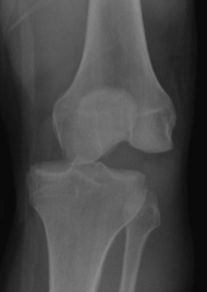

Fibula head avulsion / dislocation

Will typically have LCL and biceps femoris ligament attached

Fibular head avulsion

Fibula head avulsion and medial tibial plateau fracture